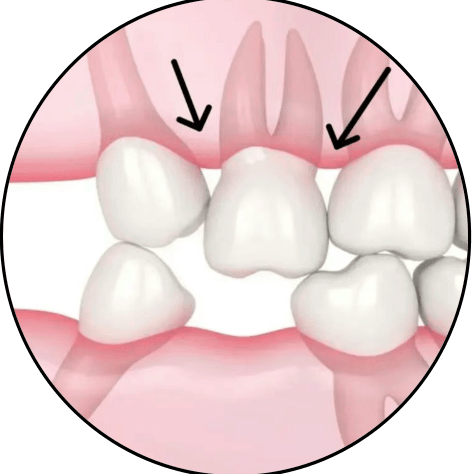

垂直型

咀嚼时由咬合力量或充填式牙尖的作用使食物从垂直方向嵌入两牙邻面,对牙龈组织损害较严重。

垂直性嵌塞的可能原因

两邻牙之间失去正常的接触关系,出现缝隙。有多种情况可能引起此种改变:邻面的龋齿破坏了正常的牙齿结构,造成了缝隙的出现;牙齿因各种原因错位或扭转造成了牙齿之间的间隙;缺失牙之后没有及时修复造成两侧邻牙向中间倾斜,造成两侧多颗牙齿之间的间隙;过度松动的牙齿与邻牙接触不佳,造成缝隙;倾斜的智齿也会造成食物易嵌塞在倾斜的空隙。